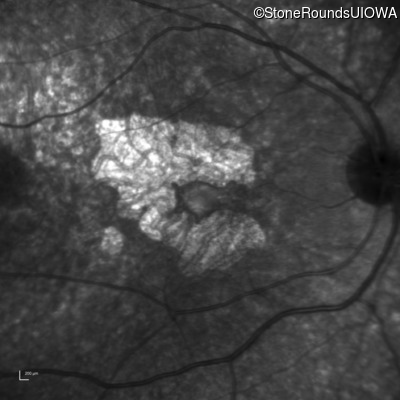

Age at visit: 30 years

This 30 year old man first noticed poor vision in dim light when he was five years old. His visual acuity began to fall in his early 20's.

Diagnosis & molecular findings

Disease Gene Allele 1 variant(s) Allele 2 variant(s) Inheritance mode

Macular Disease WDR19 His344Arg CAT>CGT Ser485Ile AGT>ATT AR